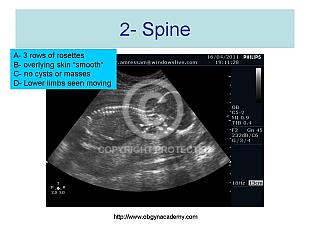

20 weeks scan checklist point 2 of 10 Fetal Spine

Standard views

1504 views